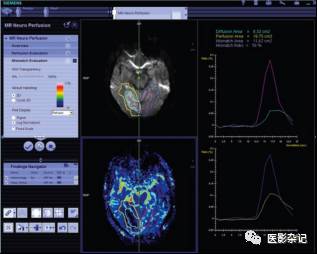

T1、T2序列是诊断绝大多数颅脑疾病的重要基础,此外,还有若干相对“高级或复杂”的扫描序列,如DWI、PWI、DTI及fMRI等。这些序列能够更好的反映新陈代谢与血流动力学信息,从而能够辅助对于神经性疾病与肿瘤学疾病的诊断。此类序列也被称做是参数化或功能化的影像,通用需要采用一些特殊的显示方式。例如,采用伪彩方式来显示。以及必须支持由用户勾画ROI,计算ROI内信号值统计特征,并且能够在时间序列上,给出信号变化时间曲线。以下图所示的灌注图像为例,原始的MRI灌注图像都是灰度的,但通常采用伪彩显示。用户往往期望能在图中手工勾勒选取任意形状的感兴趣区域,然后由软件给出该区域内的信号值统计信息,包括信号随时间的变化曲线,也就是通常所说的时间强度曲线(Time-Intensity Curve)。

*来自西门子